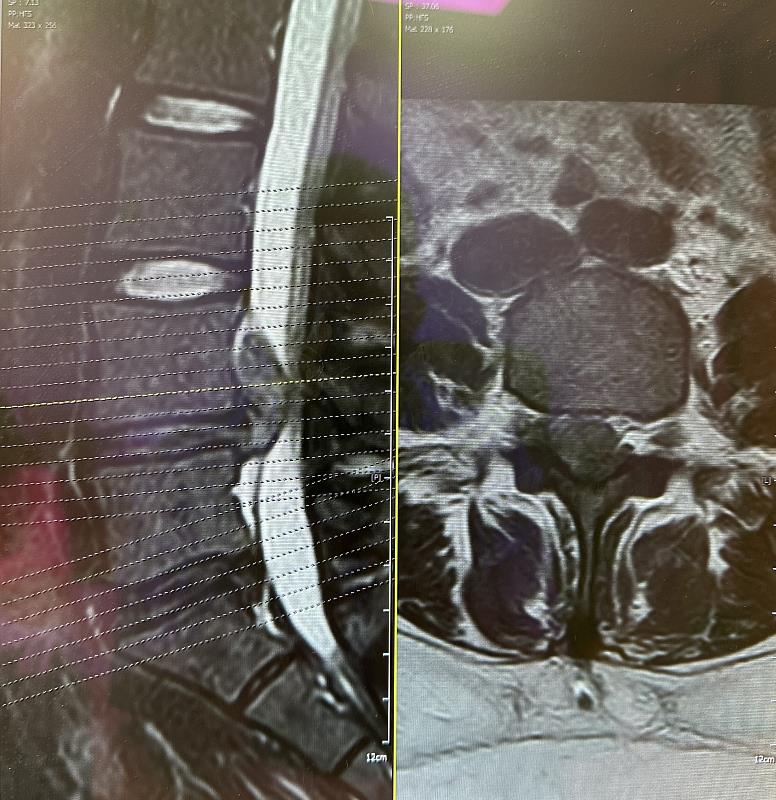

「核磁共振造影(Magnetic Resonance Imaging, MRI)是目前醫生用於偵測脊椎退化程度的主要工具,但核磁共振造影只能由影像做診療的判斷。」黃國淵主治醫師說,針對椎間盤突出目前能檢測的方法是使用 MRI,但透過影像判讀無法瞭解內部成分,椎間盤的支撐能力、髓核彈性的改變,或更細部的力學資訊。

國立成功大學生物醫學工程學系鄭友仁講座教授與成大醫學院附設醫院骨科部黃國淵主治醫師團隊攜手合作,以同步定位的奈米壓痕和拉曼光譜的創新技術深入解析椎間盤的內部狀況。透過精密檢測,能夠了解椎間盤中間髓核的狀態,進而判讀退化程度與發炎狀態,讓醫師了解嚴重程度,是否讓病患保守治療或是手術治療。該研究發表於國際生醫材料學會之官方期刊 Journal of Biomedical Materials Research 並獲選期刊封面故事 Correlation of the degenerative stage of a disc with magnetic resonance imaging, chemical content, and biomechanical properties of the nucleus pulposus (https://onlinelibrary.wiley.com/doi/10.1002/jbm.a.37490)。